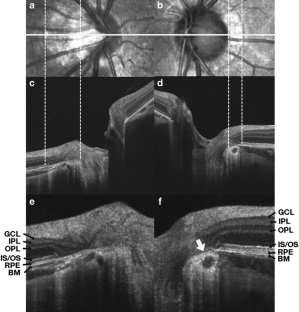

Fifty young myopic eyes with PPA (myopic PPA group), 50 aged non-myopic eyes with PPA (aged PPA group), and 50 young non-myopic eyes without PPA (control group) were enrolled. High-definition OCT scanning was used to obtain horizontal cross-sectional optic nerve head (ONH) images. By use of these OCT scans we investigated three temporal optic disc margin structures: the configuration of the border tissue of Elschnig; the cross-sectional ONH structure coinciding with the clinically detected optic disc margin; and the integrity of the retinal layers within the PPA area.

The distribution of the configuration of the border tissue of Elschnig and the cross-sectional ONH structure coinciding with the clinically detected optic disc margin of the myopic PPA group differed significantly from those of the control group (P < 0.01) whereas those of the aged PPA group did not (P > 0.05). Other than the photoreceptor layer, the retinal layers within the PPA area were more commonly impaired in the myopic PPA group than in the aged PPA group (P < 0.001).

Fig. 2